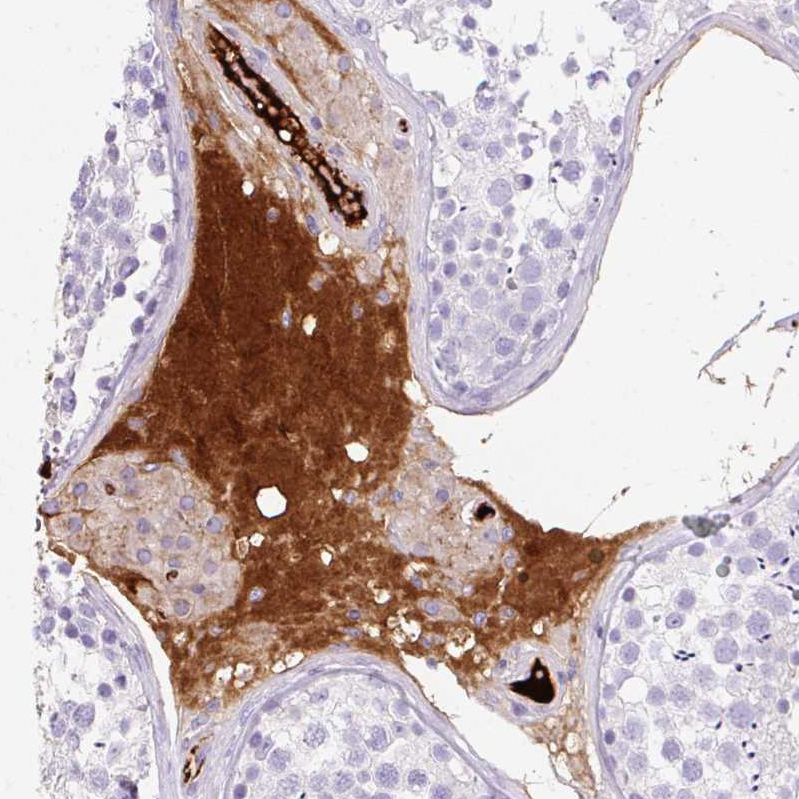

Immunohistochemical staining of human liver shows strong cytoplasmic positivity in hepatocytes.